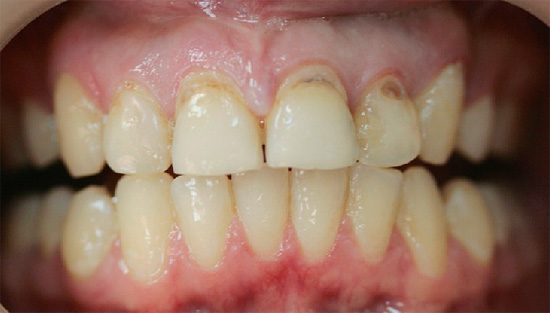

Poiché la carie di cemento è spesso combinata con la carie cervicale, per i denti anteriori, oltre ai rischi menzionati, questo è anche pieno di estetica. Macchie scure o carie cavità sui denti anteriori, specialmente se non vengono eliminati per diversi anni, provocano spesso complessi psicologici, problemi sul lavoro e nella comunicazione con il sesso opposto.

Con la posizione aperta della carie di cemento sui denti anteriori in combinazione con la carie cervicale, di norma, già allo stadio di un punto cariato senza una cavità cariata e nessun sintomo, si possono sospettare seri problemi e consultare un medico. Inoltre, in questo caso stiamo parlando della comodità di comunicare con i propri cari, amici, colleghi e altre persone. La comparsa di punti scuri, una sfumatura gessosa di smalto, le sue crepe e le schizzi al bordo con la gomma consentono di determinare la carie di cemento nella fase iniziale di sviluppo, quando può ancora "sfondare" nell'area subgengivale.